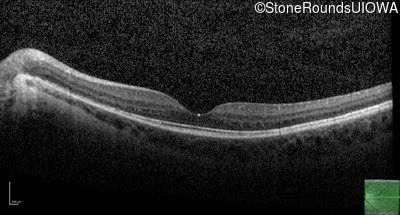

Optical Coherence Tomography - Left - 20/50

Exemplar / OCT Stack